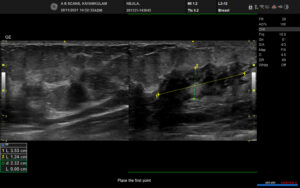

Complaints: H/o right breast pain

Case study: Well circumscribed irregular hypoechoic fluid collection measuring ~3.7 x 1.8 cm with complex mixed echogenicity showing peripheral vascularity and surrounding echogenic fat noted in the right upper midline at 12 o’clock position extending into the subareolar region.

Images:

Conclusion: Well circumscribed irregular hypoechoic complex collection in the right breast extending into the subareolar region with surrounding inflammatory changes (BIRADS category 2). – Features in favour of acute mastitis with abscess formation.